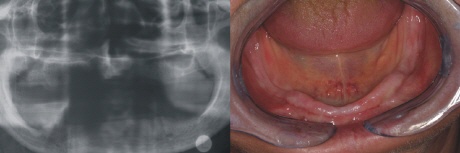

Ausgangszustand

Ein allzu typisches Problem. Die untere Prothese kann im zahnlosen Kiefer keinen Halt finden. Links sieht man das Röntgenbild und rechts die Situation im Mund.